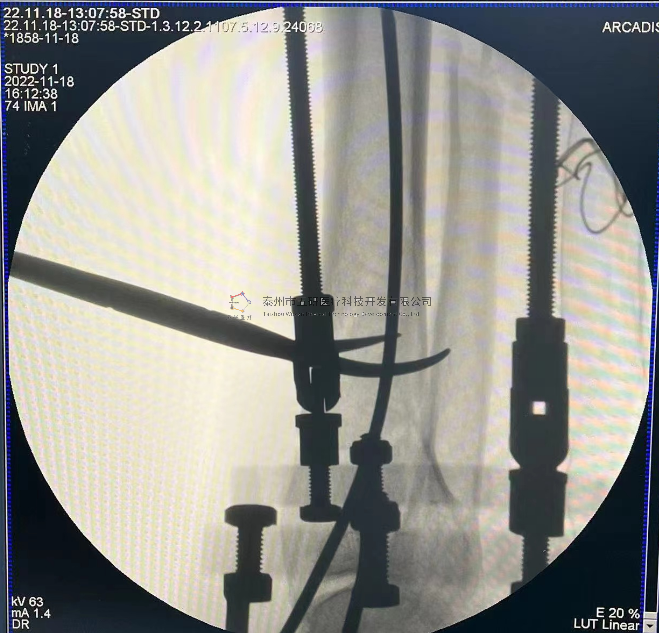

// 下肢骨折

【所屬科室】中國(guó)中醫(yī)科學(xué)院望京醫(yī)院創(chuàng)一科

【基本資料】患者,男,65歲

【患者情況】脛骨遠(yuǎn)端骨折伴腓骨骨折

【影像圖片—術(shù)后】